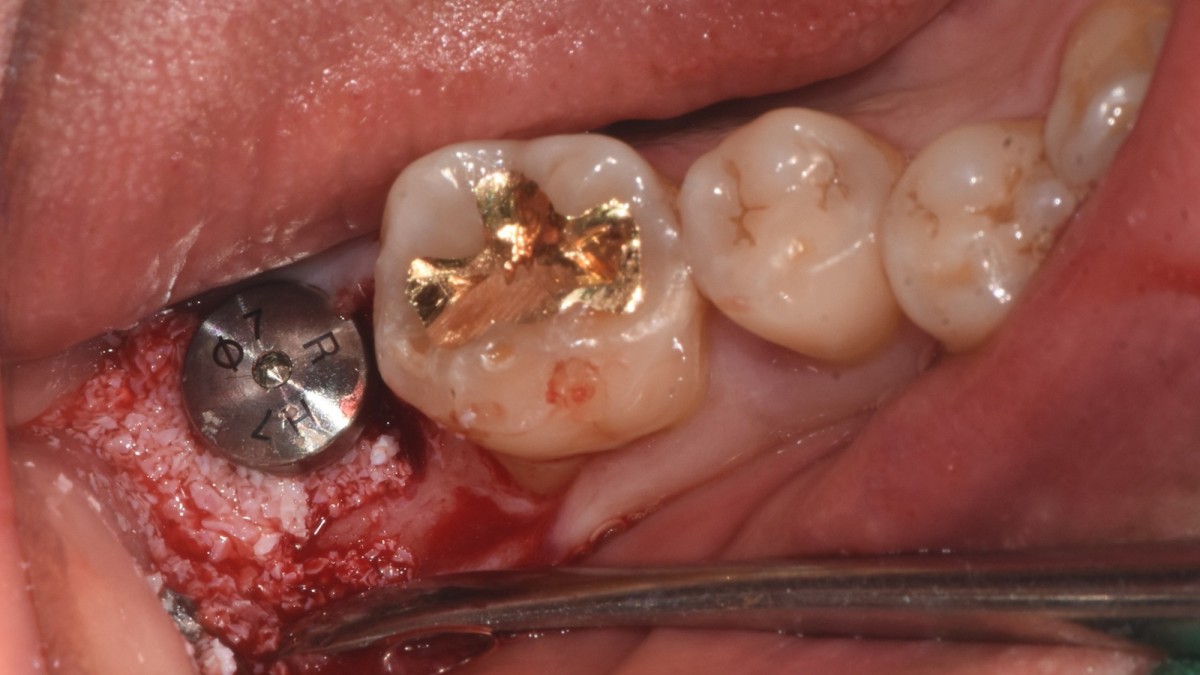

Single implant (staged) Arum NB1, f/u

A 47-year-old male patient had a crown with an ill-fitting margin and crack-tooth syndrome in the lower 2nd molar. No systemic issue.